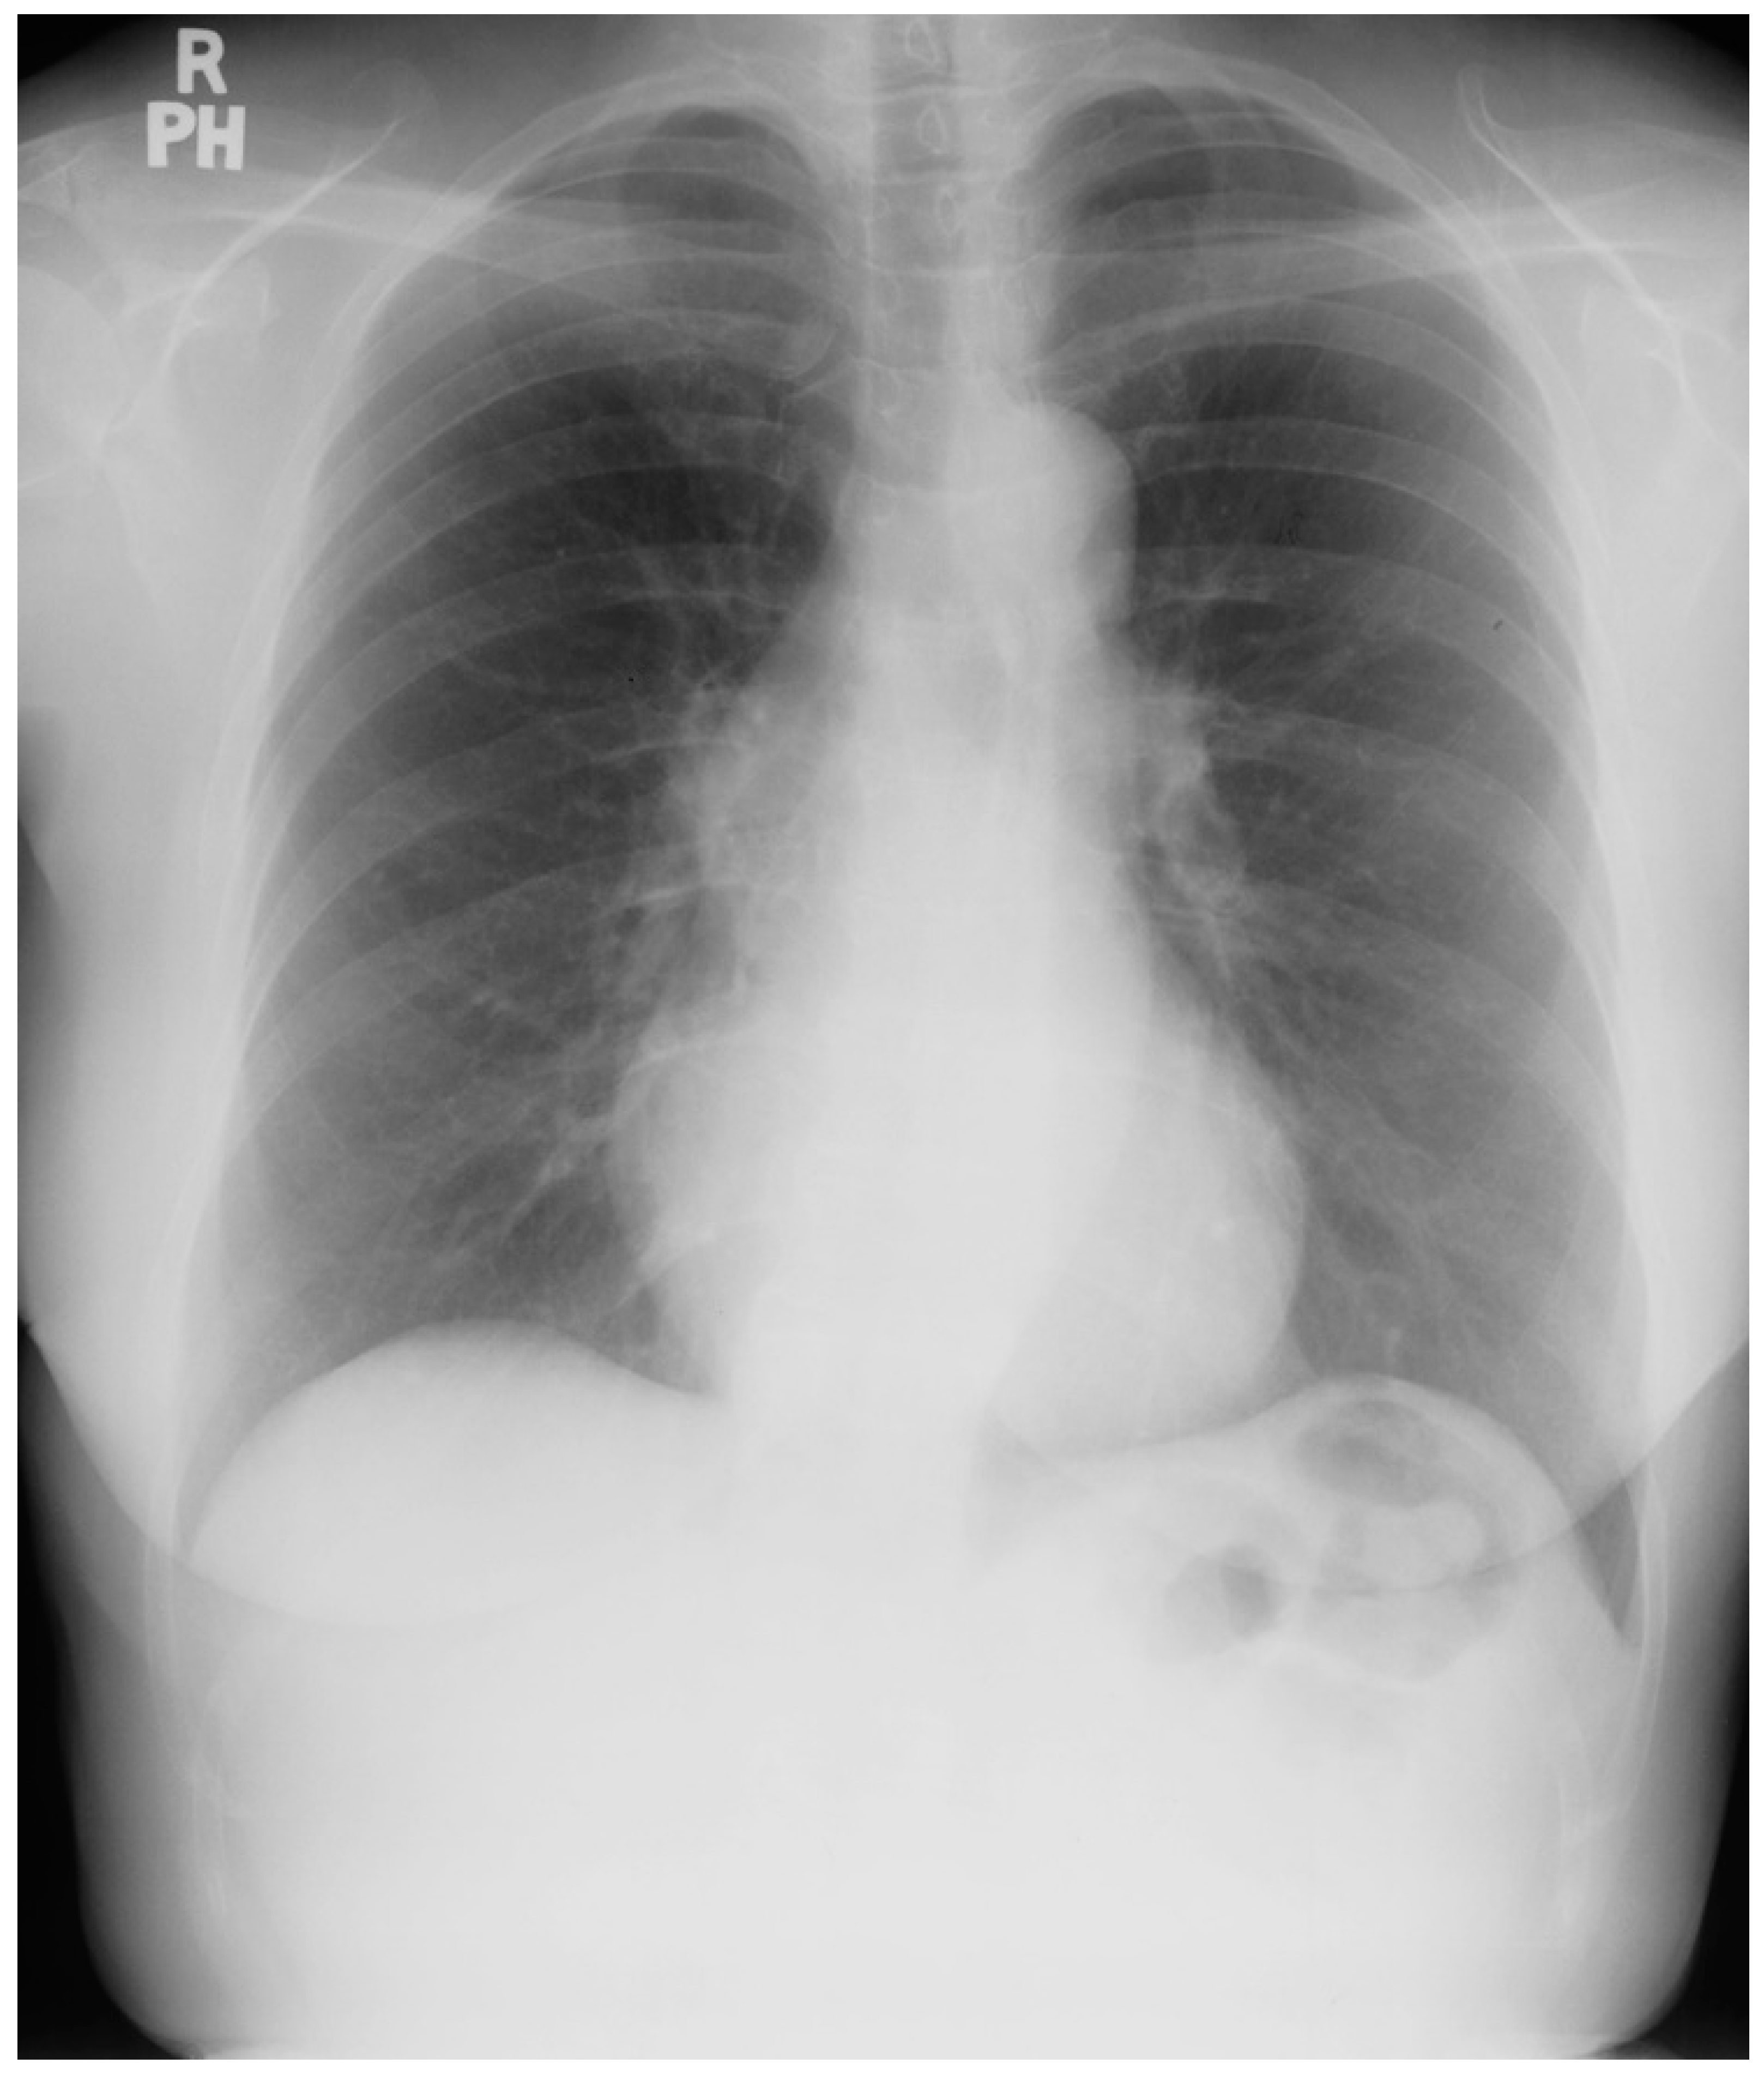

Patent Ductus Arteriosus (PDA) is a persistent communication between the aorta and the pulmonary artery, long after this vital fetal connection should have closed a few days after birth. Unoperated patients may present with a heart murmur or symptoms of shortness of breath and easy fatigue. A patient with a large and unrestricted PDA may present with Eisenmenger physiology with differential cyanosis (cyanosis of the lower extremities with normal upper extremity nailbeds) and clubbing [7]. The murmur of a moderate or large PDA is a continuous machinery murmur. In the presence of pulmonary artery hypertension (PAH) only a systolic murmur is heard. In the presence of a PDA with a large left-to-right shunt the blood pressure has a wide pulse pressure. When there is PAH from a PDA with right-to-left shunting at ductal level, lower extremity clubbing and cyanosis is found. Be sure to examine the feet. The CXR in PDA depends on the size of the shunt. A prominent proximal pulmonary artery segment indicates elevated pulmonary artery pressure (Figure 25 and Figure 26). An enlarged left atrium and enlarged left ventricle indicate a significant PDA with left-to-right shunting. Calcification in the region of the ductus should be noted because it may rupture during surgical repair [7]. Eisenmenger syndrome typically appears later in life, but patients with a large PDA are among the earliest congenital heart disease patients to present with Eisenmenger syndrome. These patients require close follow-up. Due to a high maternal mortality, pregnancy is not recommended in the presence of Eisenmenger syndrome [7]. Surgery with general anesthesia must be conducted in patients with Eisenmenger syndrome only in centers with expertise, as a fall in systemic pressure with induction of anesthesia might exacerbate the right-to-left shunt and cause prolonged systemic hypoxia, and potentially lethal vital organ injury.

Figure 25.

Posteroanterior chest X-ray of patent ductus arteriosus with Eisenmenger syndrome: this X-ray was obtained in a 56-year-old dyspneic female with Eisenmenger syndrome from an unrepaired patent ductus arteriosus (PDA). She was born in 1948 with a murmur noted at birth, at a time when no surgical intervention was possible. She was restricted from physical activity as a child and started to notice exertional dyspnea in her late teens. Cardiac catheterization at the time led to the diagnosis of Eisenmenger syndrome with PDA. This posteroanterior chest X-ray is well centered and there is a good inspiration. The cardiothoracic ratio is <0.5. The pulmonary trunk is enlarged, with calcification noted in its lateral perimeter. There is pruning of the peripheral pulmonary arteries. There appears to be exuberant callus formation at healed fractures of the right posterior eighth rib and the left posterior seventh rib.